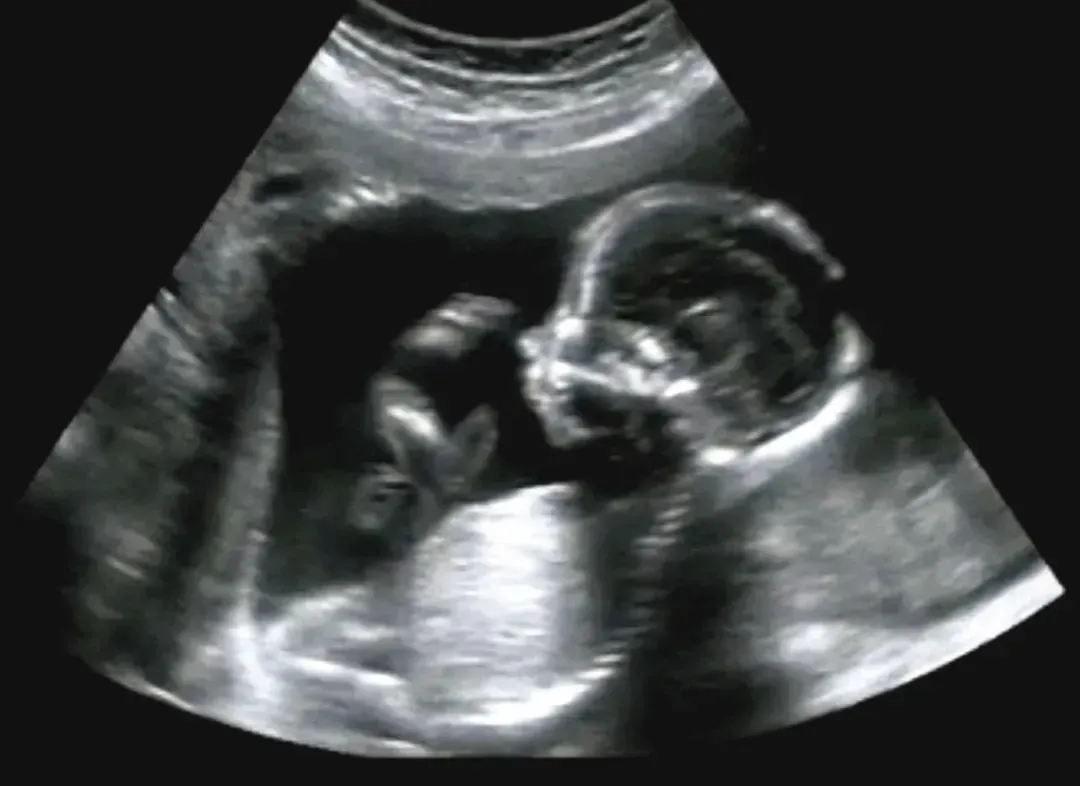

4、大排畸筛查

大排畸即中孕期胎儿超声大畸形筛查,是孕期非常重要的一项产前检查。

大排畸的筛查内容包括胎儿的头部、脑部结构、脊柱、心脏、腹部器官(如肾脏、胃、膀胱)、四肢、骨骼等。

其目的是为了排除胎儿是否存在严重结构畸形,如心脏缺陷、神经系统异常、四肢、面部、内脏器官的畸形等,以及确认胎儿的生长发育是否与孕周相符,观察胎盘位置、羊水量以及脐带情况。

大排畸筛查一般在孕期的20-24周进行,此时胎儿已发育出大部分器官,羊水量适中,且胎儿大小适宜,便于详细观察。

检查的方式可采用二维、三维或四维超声技术,其中四维彩超能提供更为直观、动态的图像,有助于医生更细致地观察胎儿结构。

即便大排畸结果正常,也应该定期复查,某些胎儿异常可能会在孕后期才会显现。

而如果大排畸结果异常,则需要配合羊水穿刺,甚至是脐血穿刺近一步确诊,便于及时采取相应的处理措施。